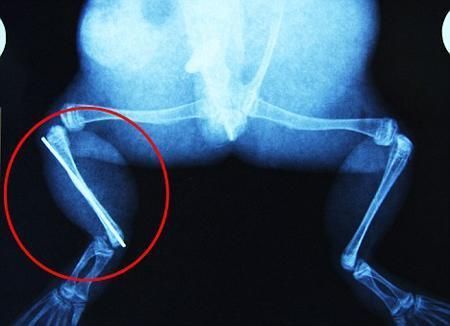

環(huán)球網(wǎng)4月2日?qǐng)?bào)道 據(jù)《每日郵報(bào)》報(bào)道,上個(gè)月,南非大牛蛙布魯萊的右小腿被鄰居家的一只狗咬到,導(dǎo)致粉碎性骨折,現(xiàn)在經(jīng)過(guò)2個(gè)小時(shí)的手術(shù),它的斷腿已經(jīng)被接上,它也因此成為有史以來(lái)第一只通過(guò)外科手術(shù)用鋼針接上斷腿的青蛙。

布魯萊的主人,居住在南非約翰內(nèi)斯堡附近的62歲的安妮·米恩斯說(shuō):“我對(duì)這只青蛙如此關(guān)心,人們一定認(rèn)為我瘋了,但是我無(wú)法眼睜睜看著它那么痛苦。青蛙因其靈活的腿腳而著稱,一想到布魯萊的腿里要留下一個(gè)薄金屬片,我就感到心痛。然而我知道,如果不進(jìn)行手術(shù),布魯萊以后就沒(méi)辦法動(dòng)彈了。因此我匆匆趕到獸醫(yī)那里,央求他給這只可憐的青蛙動(dòng)手術(shù)。這位獸醫(yī)整天救助小貓小狗,他很難理解為什么我這么擔(dān)心一只青蛙,但是最終他還是答應(yīng)了給布魯萊做手術(shù)。手術(shù)后是幾個(gè)小時(shí)的焦急等待,我們希望它能快快蘇醒過(guò)來(lái)。不過(guò)現(xiàn)在它的傷口已經(jīng)愈合,又能在花園里跳來(lái)跳去了。X光照射顯示,它會(huì)恢復(fù)的跟以前一樣!

野生生物專家安妮經(jīng)常為學(xué)校寫教材,她認(rèn)為這是人類第一次通過(guò)手術(shù)給一只青蛙接斷腿。在手術(shù)開(kāi)始階段,獸醫(yī)把少量給狗用的麻醉藥注入到這只青蛙體內(nèi),讓它失去知覺(jué)。然后他在布魯萊的斷腿上切開(kāi)一個(gè)小口,把一根小鋼針植入腿里。最后獸醫(yī)給它縫了9針,把切口縫合在一起。僅僅幾周后,布魯萊就能在安妮家附近活動(dòng)了。這只青蛙大約已有25歲,主要以嚙齒動(dòng)物、蛇和其他青蛙為食。布魯萊所屬的牛蛙種群正在不斷減小,目前只能在非洲南部的濕地里才能看到這種青蛙。